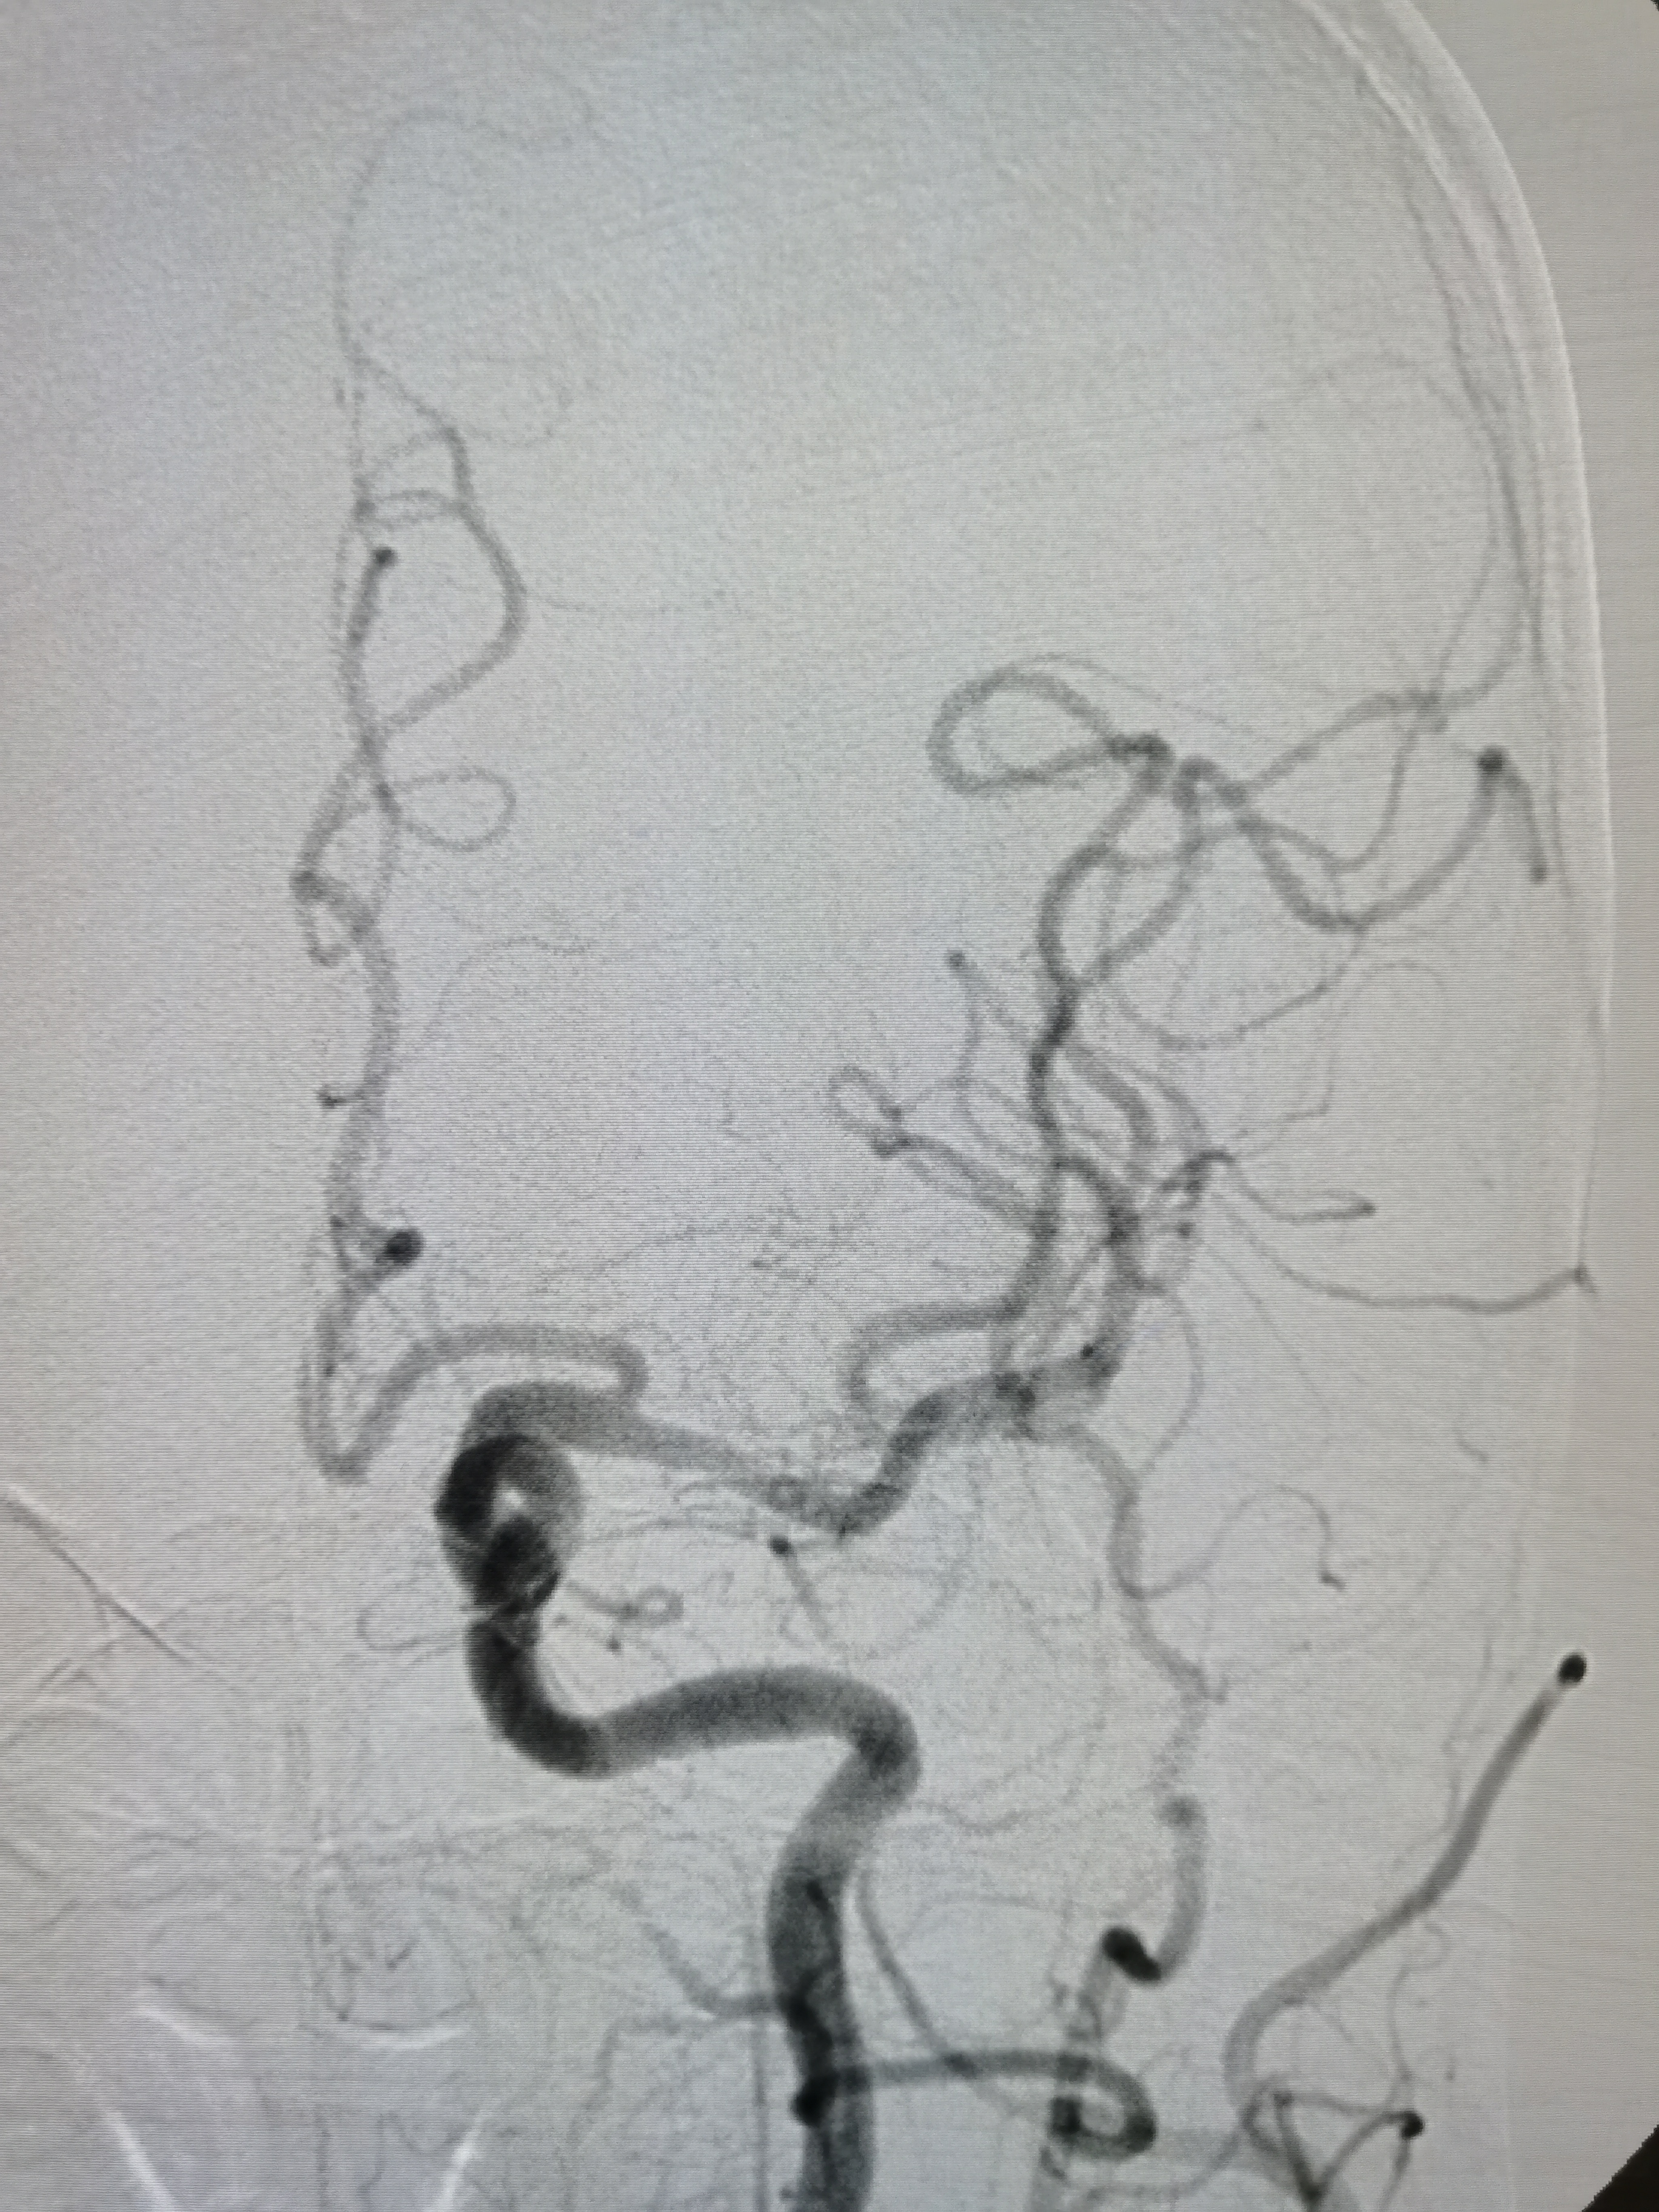

患者PXY,男性,55岁,因突发头晕、恶心、呕吐2.5小时来院。患者于2.5小时前开车过程中自觉头晕,呈昏沉感,恶心呕吐多次,变换体位时加重,无肢体无力,遂急诊来院。

1、本例患者临床表现为头晕,恶心,呕吐后循环缺血症状,急诊CT除外出血后给予静脉溶栓治疗。经内科治疗后症状逐渐改善。但患者无卒中高危因素,需完善脑血管相关检查。

2、CTA证实左椎动脉起始部重度狭窄合并血栓,系责任血管,存在急性闭塞或残存血栓脱落至基底动脉风险,需积极处理。